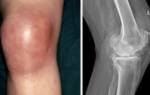

- Остеоартрит;

- Бурсит;